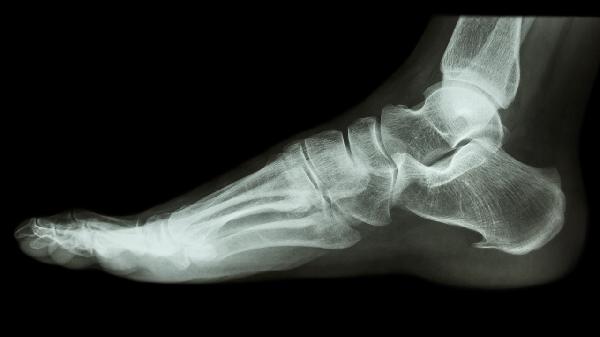

饮食需控制钠盐摄入每日<5g,多食含钾食物如香蕉、紫菜;补充蛋白质可选鲫鱼豆腐汤或乳清蛋白粉。康复期避免剧烈跑跳,建议使用前足减压鞋垫配合碳纤维支具。定期复查X线观察骨痂生长情况,若肿胀持续超过2周伴皮肤发亮需排查深静脉血栓。睡眠时穿戴渐进压力袜可预防晨起水肿,结合低频脉冲电磁场治疗仪促进骨愈合。